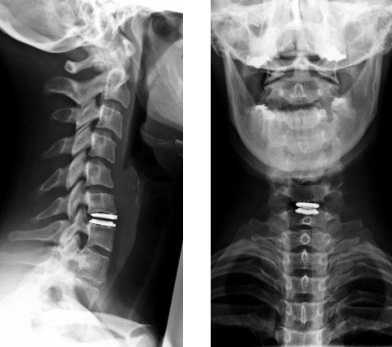

Рисунок 1 : Передний подвывих C4 по сравнению с C5 связан с увеличением зазора / дистракции фасеточного сустава. Вероятно, это связано с механизмом гиперфлексии.

Обследование начинается со стандартной рентгенографии в 3 проекциях - боковой, передне-задней (прямой) и через рот.

МРТ шейного отдела позвоночника. Острая травма. Компрессия спинного мозга, отек и контузия. Сагиттальная Т2-взвешенная МРТ.

МРТ шейного отдела позвоночника. Т2-взвешенная сагитальная МРТ. Острая травма с повреждением задних элементов позвонков и отеком спинного мозга.